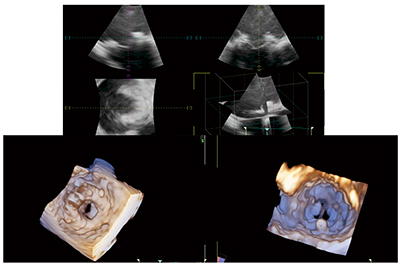

大動脈弁のBiplane modeの画像(図2 a),および3D zoomの2D画像(図2 b)と3D画像(図2 c)を示す。図2 cは大動脈弁を大動脈側から見ており,左冠動脈,左冠尖,右冠尖,無冠尖が確認できる。

図2 大動脈弁の3D TEE画像